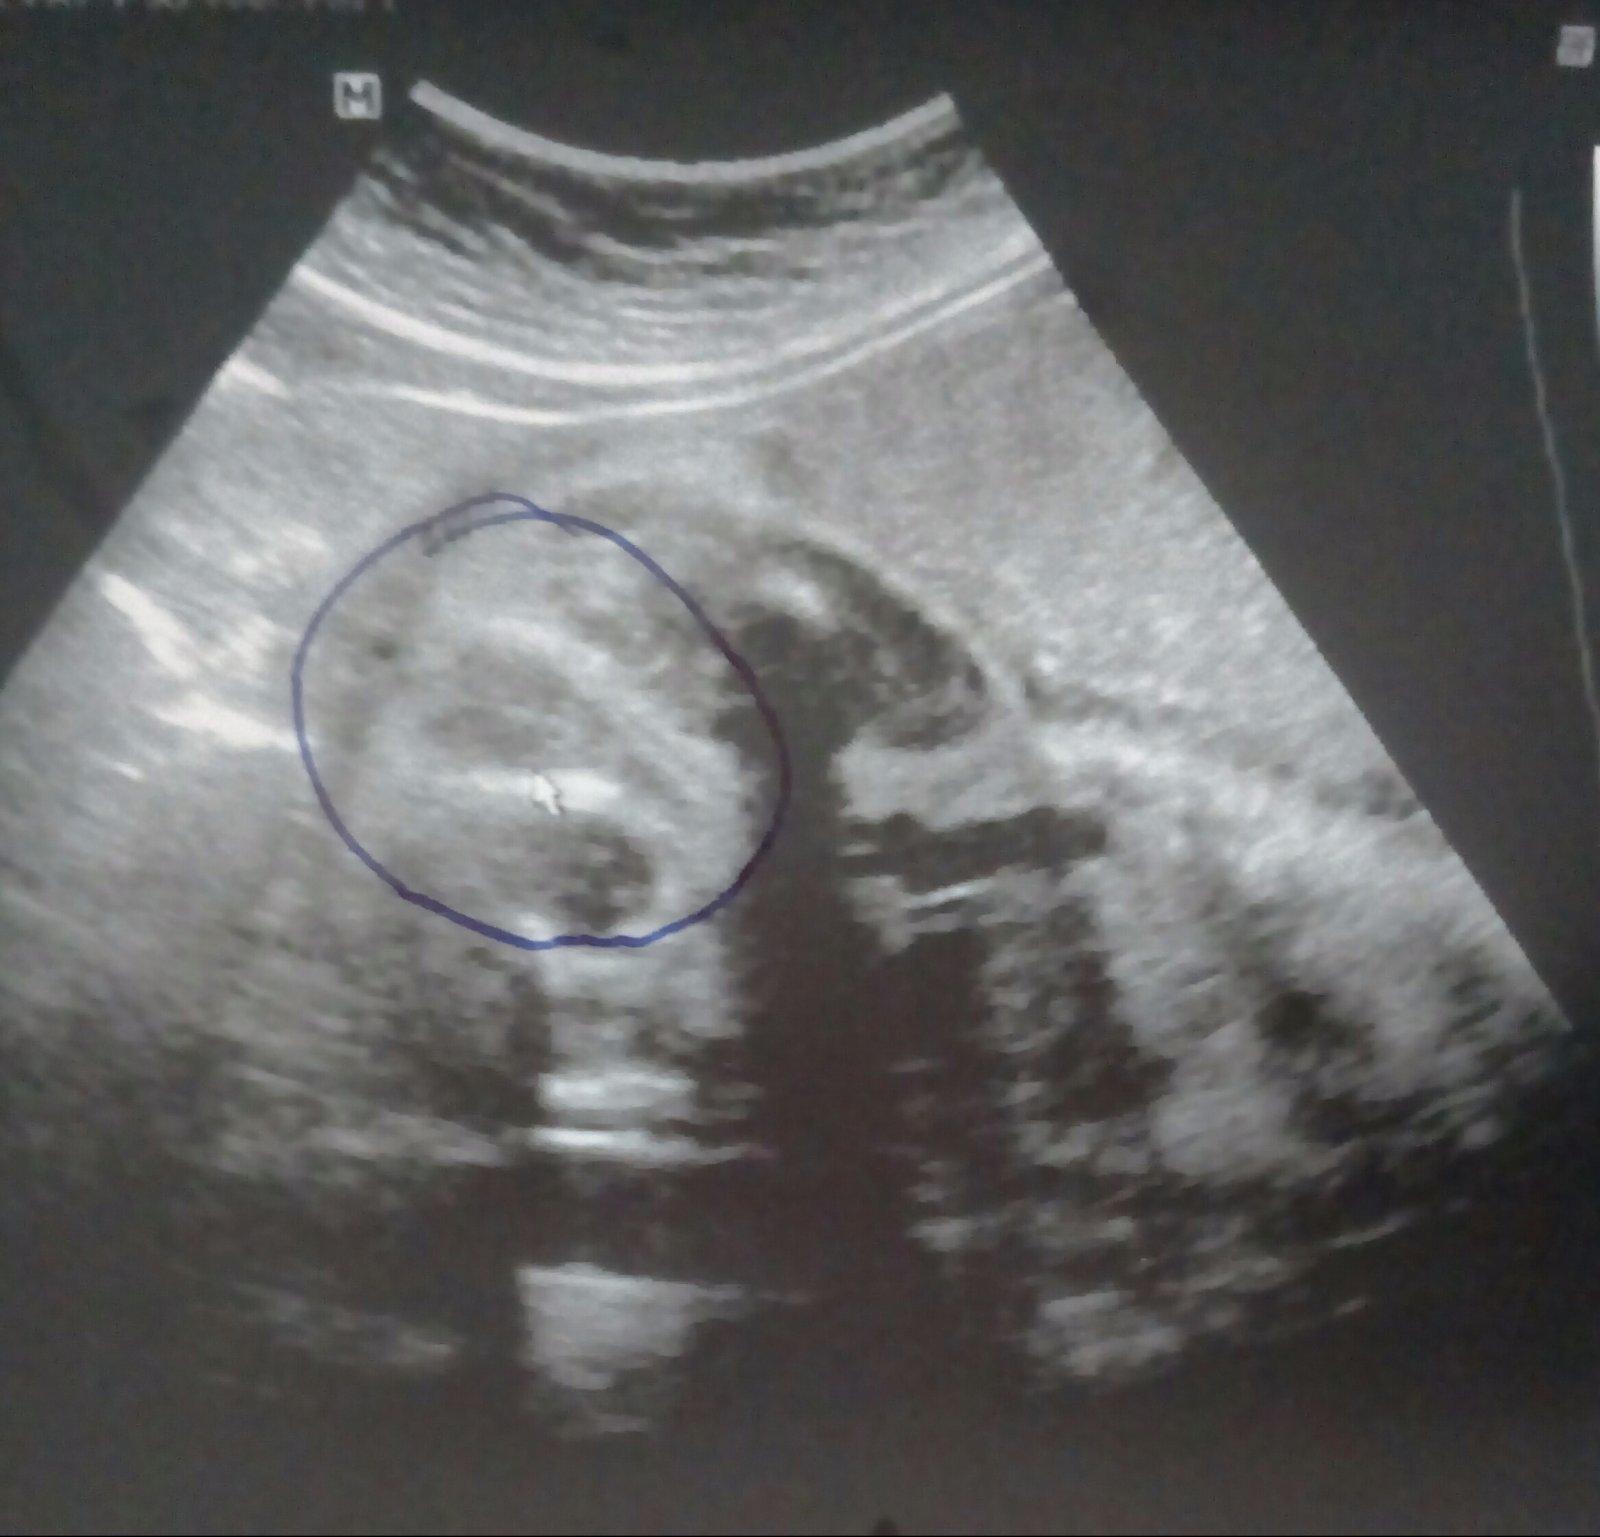

¨Z této fotky těžko soudit, na první pohled to může být holčička,ale na druhý by se dalo polemizovat, mohou to být i varlátka a to co od nich vede penis, těžko soudit, ale pokud jste ve 30tt tak už to máte za pár. My u prvního nevěděli bylo to 50 na 50 miminko bylo neustále v takové poloze že jeden doktor hádal kluka druhý holku a jiný zas řekl kluk pak můj zase změnil že holka, pak už jsme nepátrali a máme chlapečka, u druhého miminka nebylo pochyb že je to chlapeček 😀 měl nohy roztažené do široka a "anténa" nešla přehlédnout 😀

Pripadne to jako pindik kavove zrno vypada jinak. Cekam holciku a je to oval prepuleny. Podobne vypadali kluci na utz. Zalezi co vam rekli na genetice. Typuji kluk.